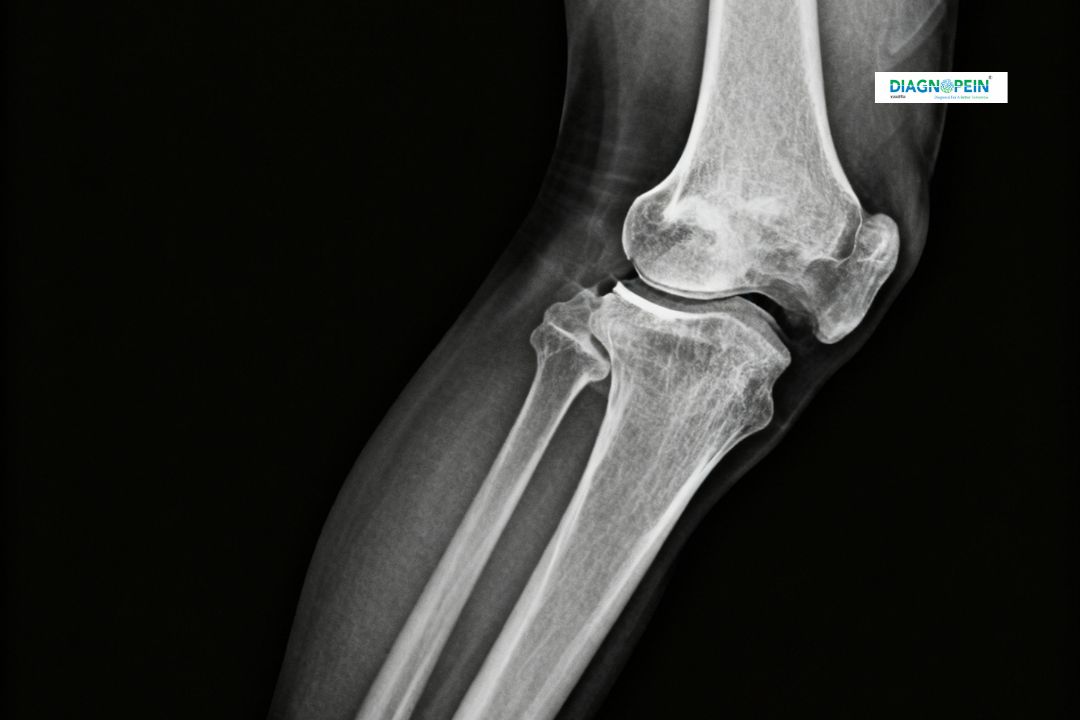

An X-Ray Right Leg Lateral View is a specialized imaging test that captures detailed side-view images of the leg bones — including the femur, tibia, fibula, and knee joint. This diagnostic imaging technique helps doctors evaluate bone fractures, joint dislocations, and bone density changes. At Diagnopein in Karad, advanced digital X-ray systems ensure crystal-clear results with minimal radiation exposure.

The X-Ray Right Leg Lateral View plays a crucial role in orthopedic and trauma assessments. Its importance lies in its ability to visualize structural alignment and subtle fractures that might be missed in a standard anteroposterior (AP) view.

The X-Ray Right Leg Lateral View focuses on key anatomical parameters that help doctors assess structural integrity and functional alignment of the leg bones. The main evaluated parameters include:

1. Bone density and continuity

2. Fracture lines or displacement

3. Knee and ankle joint spacing

4. Soft tissue swelling or fluid accumulation

5. Alignment and angulation of bones

Early and accurate interpretation of these findings helps orthopedic specialists in Karad decide on immediate care, surgery, or physiotherapy.